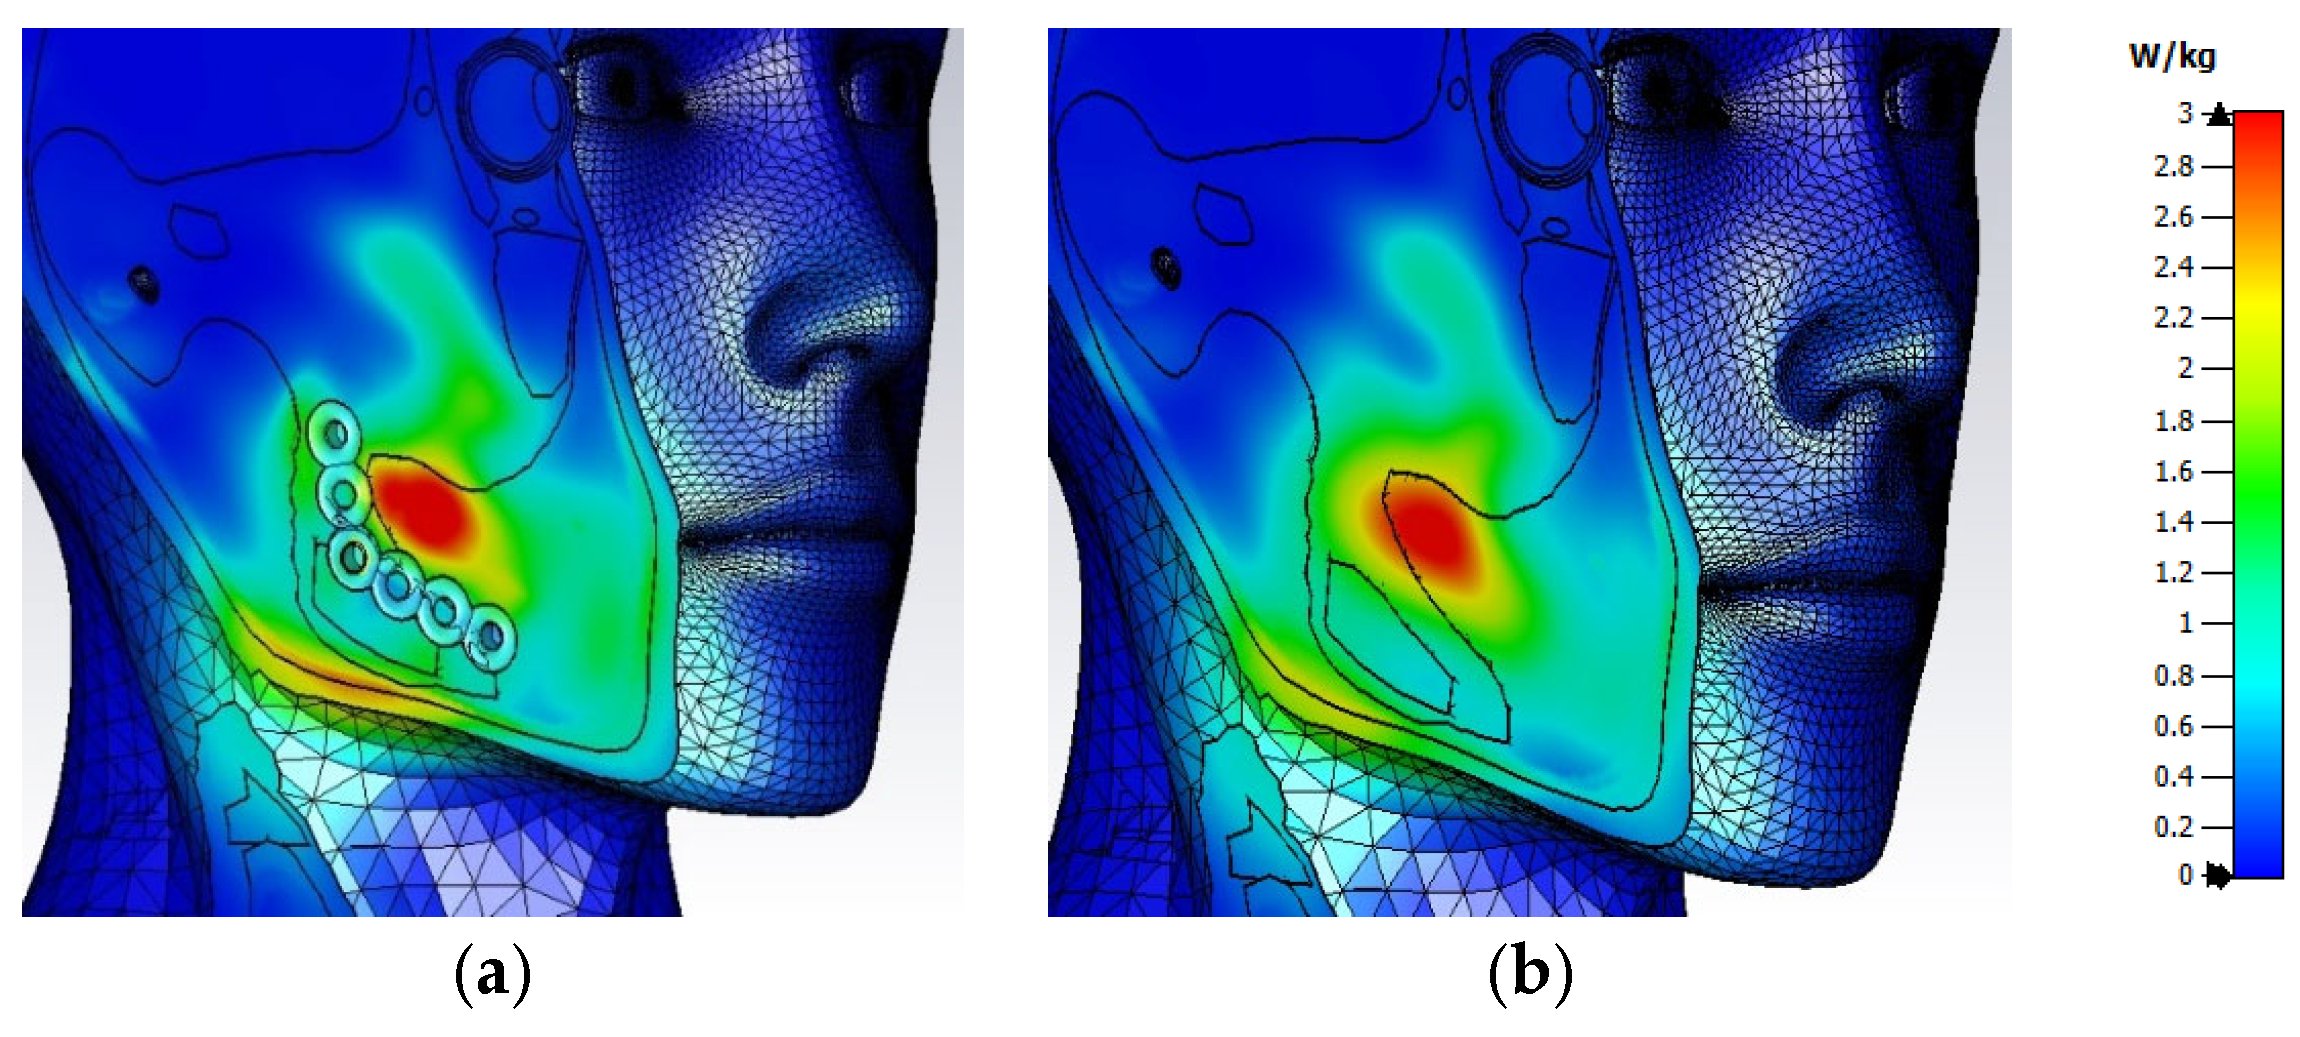

3.1. Electric Field Distribution Inside the User’s Head

3.2. Distribution of SAR Values Within the Model of the Head of a User